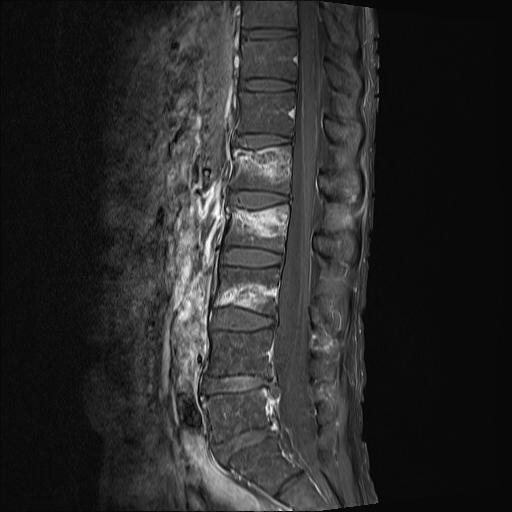

MRI 영상입니다.

가운데 하얀 부분이 골절이 되었다는 얘기입니다. 아시다시피 허리뼈는 5개인데 보이시죠?

1,2,3번 압박골절의 흔적.